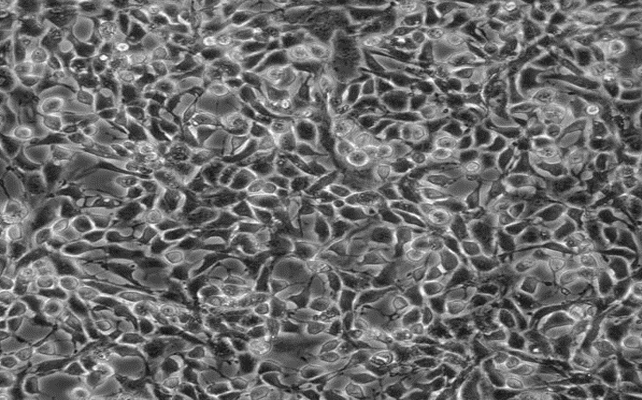

A375.S2;人黑色素瘤细胞

Lncap;人前列腺癌细胞

HSF;人皮肤成纤维细胞

HDF-a;人真皮成纤维母细胞-新生

TE353.SK;人正常皮肤细胞

HTR-8;人滋养细胞

RWPE-2;人正常前列腺上皮细胞

RWPE-1;人正常前列腺上皮细胞

231-luc;乳腺癌细胞